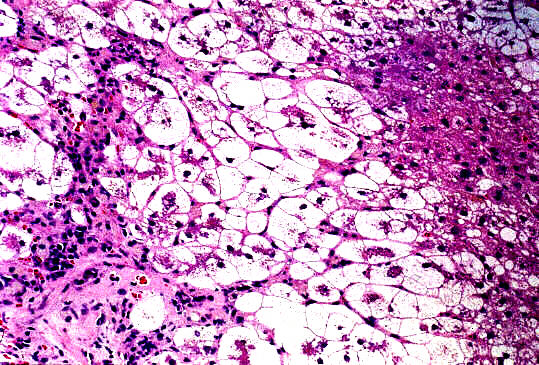

標本;HE,Azan,HBsAgオルセイン&鍍銀の4染色

- 小葉構造;P-P bridging hepatic necrosisをみるも保持されている

- 門脈域;中等度までの線維性拡大、中等度までの単核球主体の炎症性細胞浸潤、小葉間胆管の障害像、細胆管増生、胆汁栓

- 実質域;架橋形成性壊死 (bridging hepatic necrosis)、肝細胞の風船様膨化と再生性肝細胞、小ないし中滴性脂肪沈着を部分的にみる、羽毛状変性と風船様膨化、合胞性多核巨細胞の出現、ロゼット形成(偽腺管構造)、胞体内凝集傾向、核内空胞

肝細胞にビリルビン色素、Ground-glass所見は認めない

HBsAgオルセイン;陰性(Marcophage or Kupffer's cellsに陽性;Ce-L)

病理組織診断;急性肝炎、架橋形成性壊死を伴う(重症型)

Acute hepatitis with bridging necrosis

1.Giant-cell hepatitis (Postinfantile giant-cell transformation in hepatitis, by Devaney K, Goodman ZD & Ishak KG, in 1992)

2. Syncytial giant-cell hepatitis-sporadic hepatitis with distinctive pathological features, a severe clinical course, and paramyxoviral features (by Phillips MJ, et al in 1991)